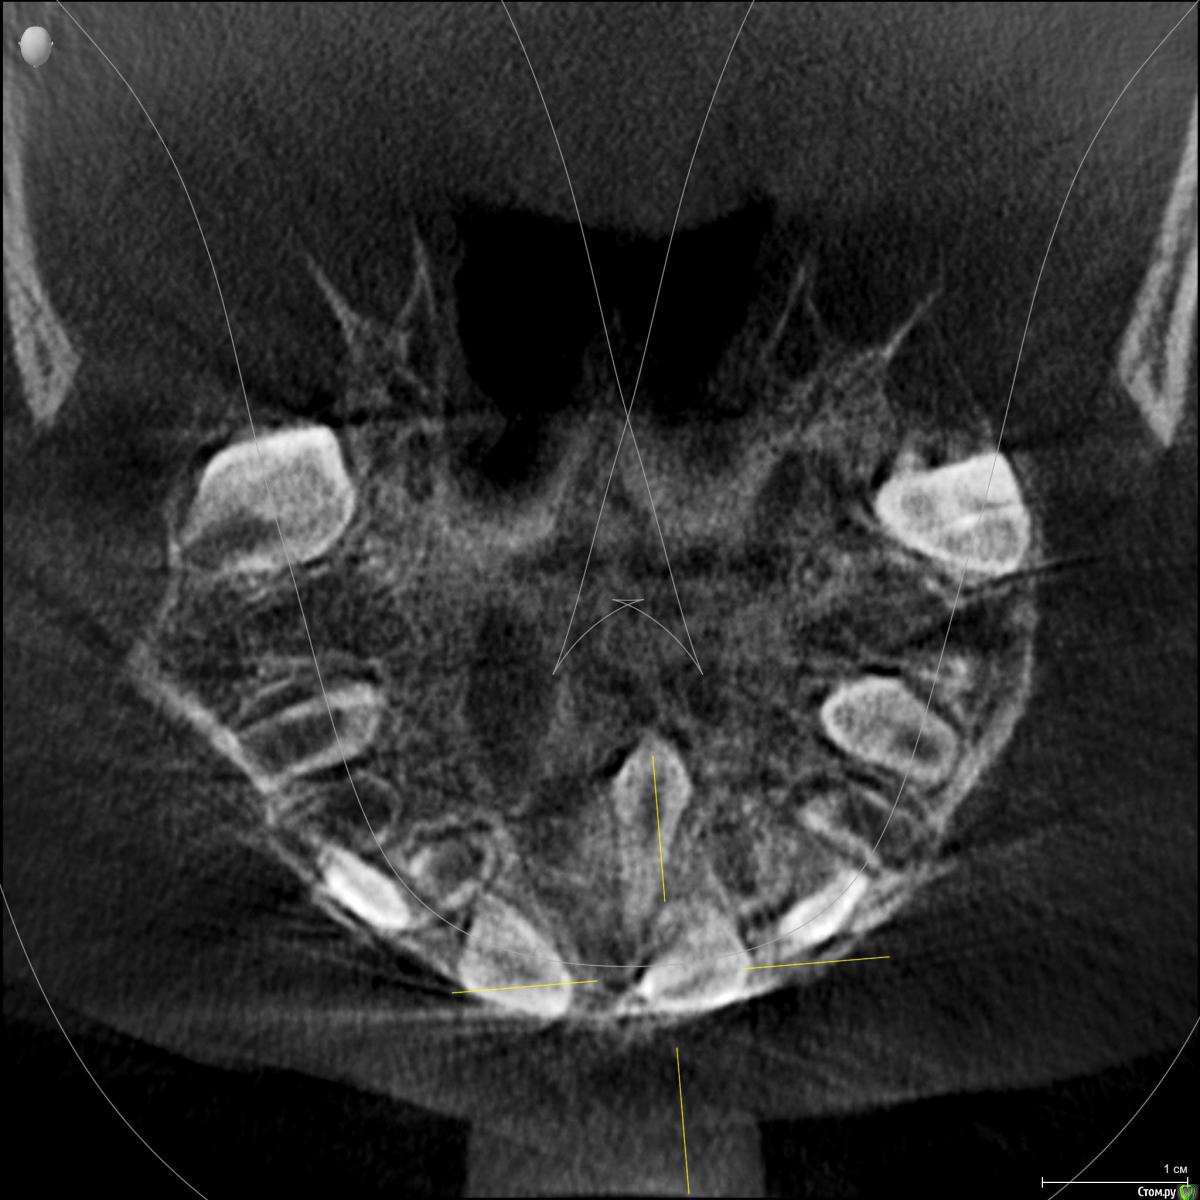

Ребенок 6 лет.

Буду благодарна за Ваше видение картины сверкомплектных и возможные планы варианты лечения.

По теме интересует какие лишние зубы можно дождаться и удалить после прорезывания, какие требуют оперативного вмешательства, какие сроки, тот что на месте 11 не вниз корнем?

Были в 4 клиниках, случай не типичный, варианты лечения разные. От ничего не делать ждать, до резать удалять. Начинали с 2 сверхкомплектов, потом нашли еще два.